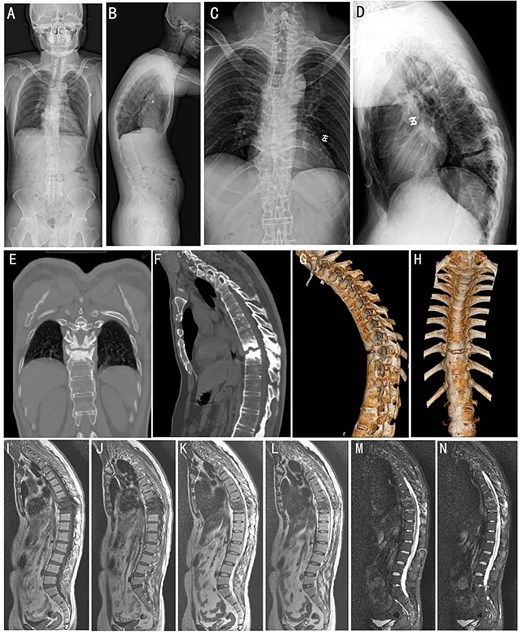

A 35-year-old male manual laborer presented to the spinal surgery department with a 5-year history of persistent chest pain and a 1-year history of progressive weakness and sensory disturbance in bilateral lower limbs. The patient denied any history of fever and trauma. Physical examination revealed marked kyphosis deformity of the thoracic spine and restricted spinal mobility. A neurological evaluation demonstrated reduced muscle strength in the left lower extremity (Grade II), bilateral positive “4” tests, and positive Babinski signs in both lower limbs. Laboratory investigation revealed HLA-B27 positivity. Inflammatory markers were elevated, with a sedimentation rate of 30 mm/h and a C-reactive protein level of 17 mg/l. Plain radiographs and computed tomography (CT) scans demonstrated the characteristic appearance of a “bamboo spine” that is consistent with advanced AS. A narrowed intervertebral space at T9-T10 vertebrae and prominent ossification of the paravertebral ligaments were observed (Fig. 1A–H). Magnetic resonance imaging (MRI) demonstrated the destruction of the T9-T10 vertebral bodies (Fig. 1I–N).

Preoperative imaging studies. (A and B) Full-length orthopantomogram of the spine. (C and D) Anteroposterior and lateral X-ray of the thoracic spine. (E and F) Sagittal and 3D reconstruction CT images (G and H) of the thoracic spine. Whole-spine MRI images of T1-weighted (I and J), T2-weighted (K and L), and short tau inversion recovery sequences (M and N), respectively.